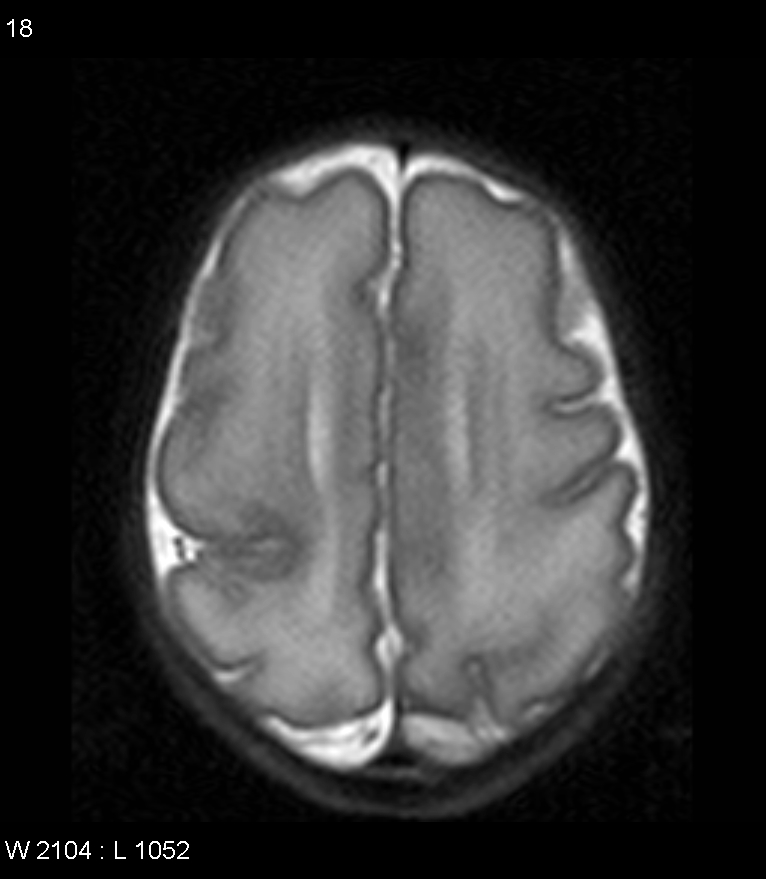

Examples of Typical MR Findings: Explore a range of typical magnetic resonance imaging (MRI) findings in patients with epilepsy. From hippocampal sclerosis and focal cortical dysplasia to more subtle abnormalities like cortical malformations, this section will highlight common and distinctive imaging features that help pinpoint the underlying cause of epilepsy.